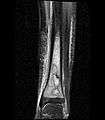

Coronal fat suppressed STIR image showing, bone marrow and subcutaneous edema as well as subperiosteal edema. The thin hypointense rim surrounding the intramedullary collection represents the reactive interface between the abscess and the body's attempt to wall it off.